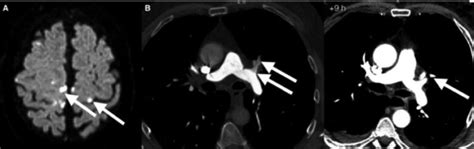

Knowing the symptoms of decompression sickness is super important, guys, especially if you or someone you know is involved in diving or high-altitude activities. These symptoms can pop up anywhere from a few minutes to even 24 hours after a pressure change, so it’s not always immediate. The most common and often the first sign is joint pain , often called ‘the bends.’ This pain can be pretty intense and usually affects the shoulders, elbows, and knees. It’s like a deep, throbbing ache that makes moving difficult. Beyond joint pain, you might experience other issues. Skin manifestations can include itching, a mottled rash (known as skin mottling), or even small red bumps. Some people report a feeling of pins and needles, numbness, or tingling, which is a sign that bubbles might be affecting nerves. Neurological symptoms are some of the most concerning and can range from dizziness, vertigo, and confusion to more severe issues like blurred vision, difficulty speaking, weakness or paralysis in limbs, and even loss of consciousness. Respiratory symptoms can also occur, such as shortness of breath or chest pain, which can indicate bubbles affecting the lungs. If you experience any of these symptoms after a dive or a rapid ascent, it’s absolutely crucial to seek medical attention immediately. Don’t try to tough it out. Divers typically use the phrase ‘when in doubt, get it out,’ meaning if you suspect DCS, get to a recompression chamber or medical professional. Early recognition and treatment significantly improve outcomes. So, keep this list handy and stay vigilant. Your health and safety are paramount, and recognizing these signs could be a lifesaver.

So, what happens if, despite all precautions, someone experiences decompression sickness ? The primary and most effective treatment is recompression therapy , often administered in a hyperbaric chamber . This is where the magic happens, guys. The patient is placed in a special chamber where the air pressure is gradually increased. This process does a couple of things: first, it shrinks the nitrogen bubbles that have formed in the body, relieving the pressure on tissues and blood vessels. Second, it helps to re-dissolve the nitrogen back into the body fluids, but in a controlled manner. Once the bubbles are managed, the pressure in the chamber is slowly decreased, mimicking a slow ascent, allowing the nitrogen to be safely off-gassed through the lungs. This controlled decompression is critical to prevent re-forming bubbles. The duration and depth of treatment depend on the severity of the symptoms and the individual’s response. In some cases, multiple sessions in the hyperbaric chamber may be necessary. Oxygen therapy is also a crucial component of treatment, both during recompression and sometimes even at surface pressure. Breathing pure oxygen helps to speed up the elimination of nitrogen from the body. For less severe cases, or as an adjunct to recompression, medical professionals might also use medications to manage symptoms like pain and inflammation. However, it’s vital to understand that recompression therapy is the cornerstone of treatment. If you suspect DCS, the immediate priority is to get the affected person to a hyperbaric facility as quickly as possible. Prompt treatment is key to minimizing long-term complications and ensuring a full recovery. Remember, if you’re diving, always know the location of the nearest hyperbaric facility and have an emergency action plan in place.